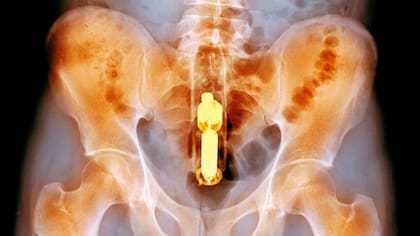

En este extremo del cuerpo, también se encontraron cosas dentro del ano y el recto. Entre 66% y 85% de los que llegan a urgencias con esa queja son hombres. Uno de los mayores problemas con objetos extraños en el ano o el recto es que se pueden atascar, obstaculizando el movimiento natural de la deposición intestinal. Con el tiempo, esto puede causar un ensanchamiento significativo del tracto con el riesgo de una perforación o ruptura del intestino.

Hay muchas razones por las cuales las personas se meten objetos extraños en el ano, desde las más comunes razones eróticas hasta las menos comunes para tratar el estreñimiento.

Aunque que las razones son diversas, la variedad de objetos encontrados por esos lares es mucho mayor. Incluyen manzanas, berenjenas, cepillos, lapiceras, zanahorias, latas de pesticidas, latas de desodorante (con las que se corre el riesgo de incendio durante la cirugía para retirarlas), vasos, botellas de refresco, bolas de béisbol y probablemente el más doloroso, un coco entero.

El problema con los objetos extraños en el recto es que los esfínteres que mantienen tus heces adentro, hacen lo mismo que los objetos que son introducidos más allá de estos.

Muchos pueden estirar la pared muscular del recto hasta el punto en que no puede generar suficiente fuerza para expulsar el objeto, lo que significa que los cirujanos usualmente tiene que abrir al paciente para retirarlos.